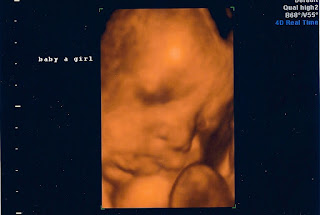

We found out their genders =)

Natalia

Noah